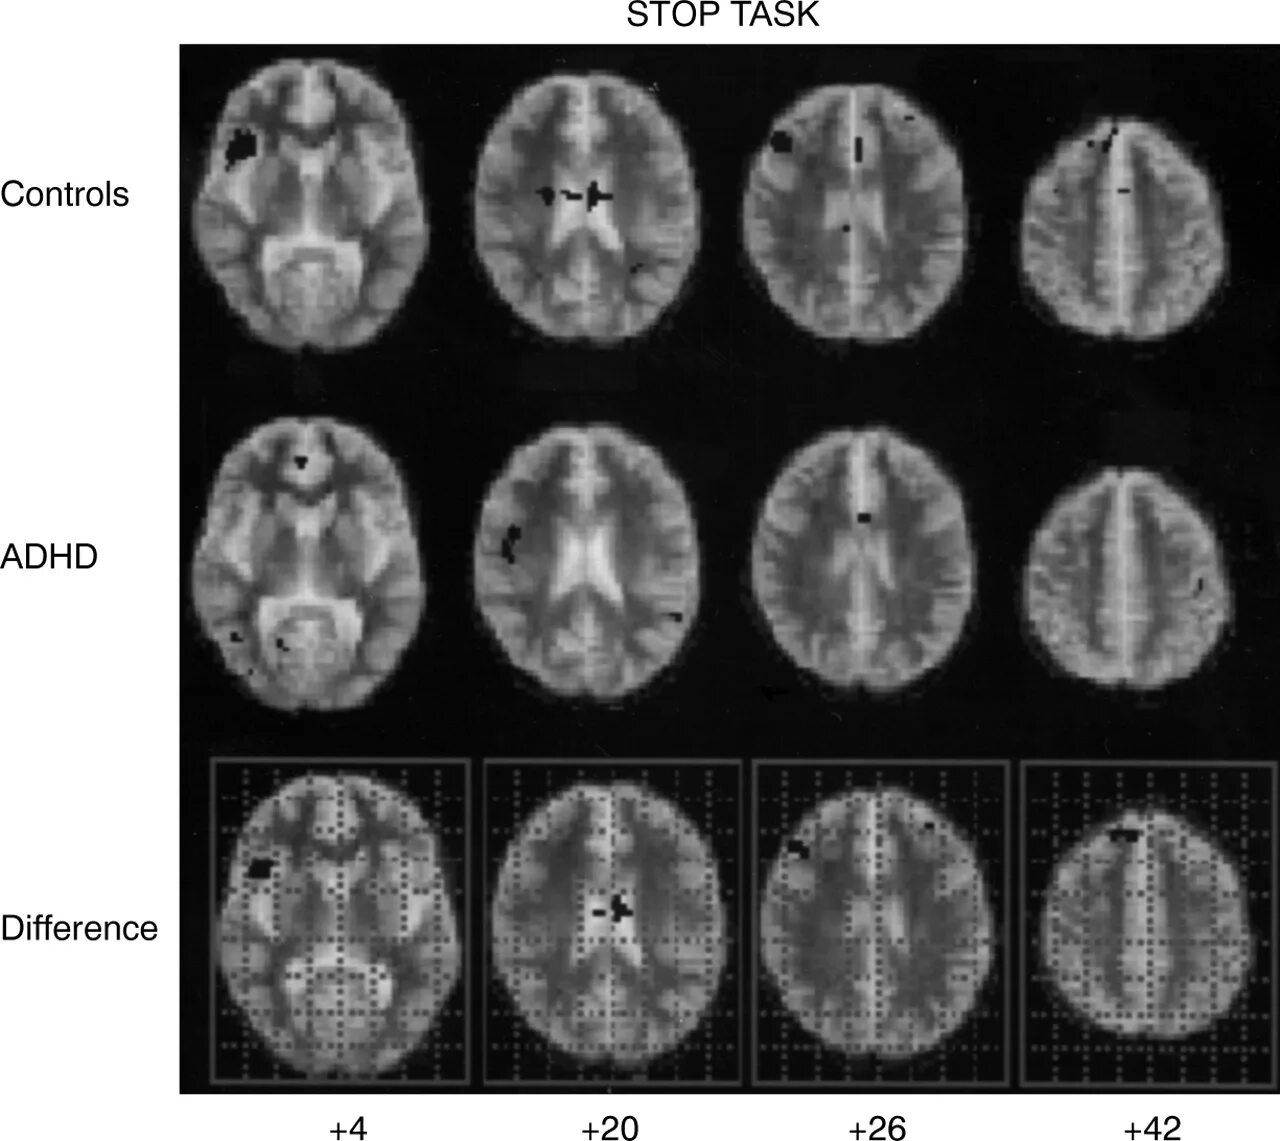

Task stop